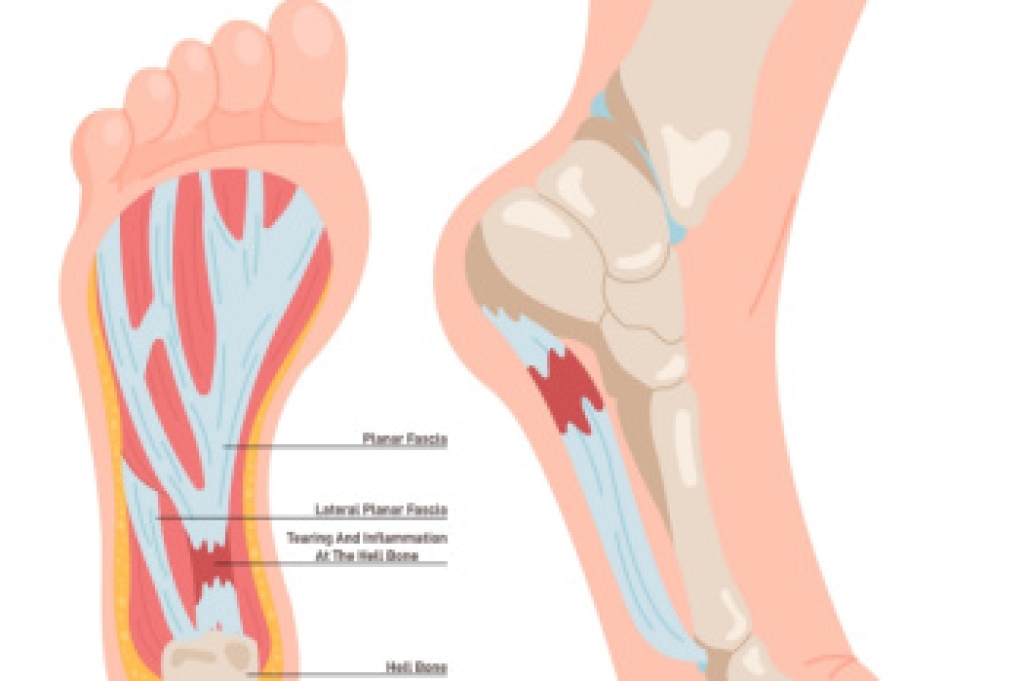

Sever's disease is often experienced by active children aged nine to 14. It occurs when the child’s calf muscle and Achilles tendon excessively pull on the growth plate of the heel bone, or calcaneus, which is still developing until about age 15. Sever’s disease typically arises in young athletes, whose vigorous activities put additional strain on their heels. Children may experience pain along the sides of their heels, which intensifies when they stand on tiptoes or run. Some may also notice warmth and swelling in the affected area. A diagnosis is usually based on these symptoms, as X-rays, while helpful for ruling out issues like bone cysts or stress fractures, cannot confirm Sever's disease. Relief options include using heel pads to reduce tendon strain, night splints to stretch the calf muscles, or in severe cases, a cast to immobilize the area. If your active child is experiencing heel pain, it is suggested that you schedule an appointment with a podiatrist for a full exam and appropriate treatment for Sever’s disease.

Sever’s disease is also known as calcaneal apophysitis, which is a medical condition that causes heel pain I none or both feet. The disease is known to affect children between the ages of 8 and 14.

Sever’s disease occurs when part of the child’s heel known as the growth plate (calcaneal epiphysis) is attached to the Achilles tendon. This area can suffer injury when the muscles and tendons of the growing foot do not keep pace with bone growth. Therefore, the constant pain which one experiences at the back of the heel will make the child unable to put any weight on the heel. The child is then forced to walk on their toes.